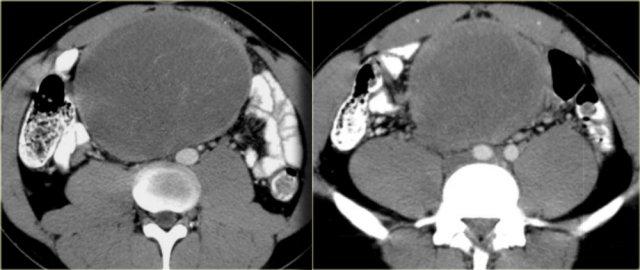

Hình bên trái là bệnh nhân nam 33 tuổi than phiền về tình trạng bụng ngày càng to, cảm giác đầy bụng và sờ thấy khối ở bụng.

Trước tiên hãy nghiên cứu các hình ảnh bên trái rồi tiếp tục xem hình MRI.

Hãy tìm các đặc điểm hình ảnh hữu ích trong chẩn đoán phân biệt.

Trước hết, đây là tổn thương có bờ rõ với giảm tỷ trọng trên CT.

Có ngấm thuốc nhẹ xung quanh tổn thương và một số dải ngấm thuốc nhỏ bên trong tổn thương.

Trên MRI, tổn thương giảm tín hiệu trên chuỗi xung T1W như dự kiến.

Trên chuỗi xung T2W, tổn thương tăng tín hiệu tương đối.

Kết hợp với giảm tỷ trọng trên CT, điều này cho thấy có chứa mucin bên trong tổn thương.

Đặc điểm này rất gợi ý chẩn đoán u xơ mạc treo.